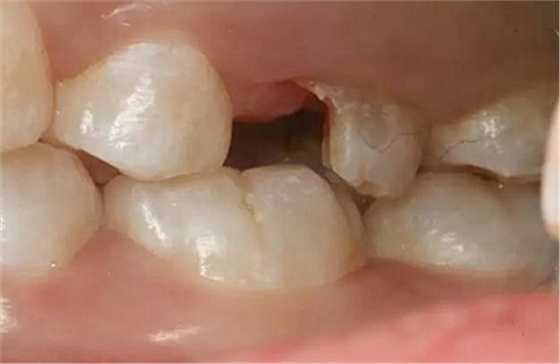

患者男性,35歲,B6銀汞充填后食物嵌塞,要求重新充填,口內(nèi)檢查見B6近中鄰頜面銀汞充填物,局部缺損,有繼發(fā)齲,去除原充填物及繼發(fā)齲,發(fā)現(xiàn)齲壞位于牙齦下方,給予冠延長手術(shù),同期嵌體預(yù)備,后一次性取模。(同樣設(shè)計為齦上邊緣)

硅橡膠取模后,灌注模型,科爾琥珀樹脂制作嵌體。

一周后拆線,口內(nèi)試戴合適,粘結(jié)嵌體。